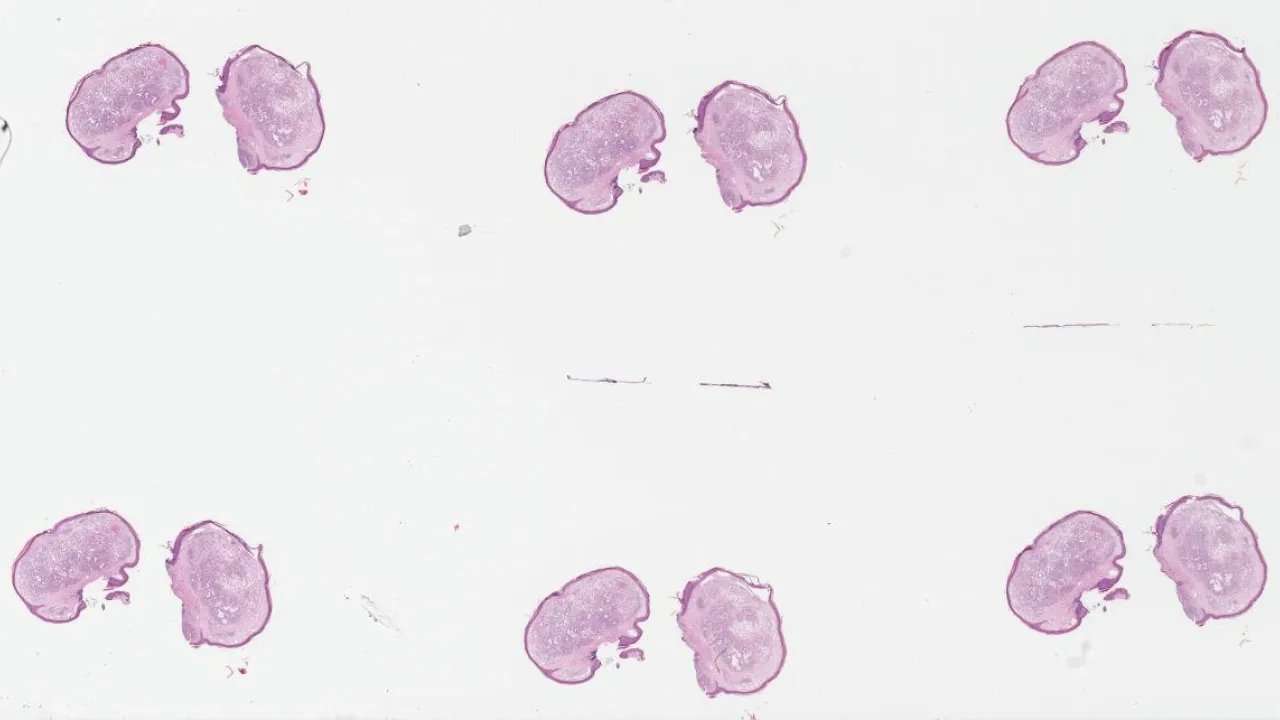

Kidney, Metanephric adenoma